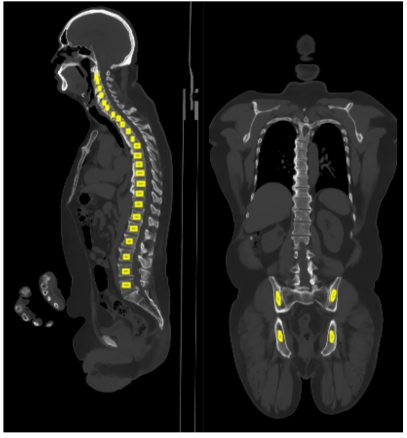

The cervical vertebra (CV: C1-C7), thoracic vertebra (TV: T1-T12), lumbar vertebra (LV: L1-L5), and pelvis regions were first segmented using the TotalSegmentor toolbox [32] installed in 3D Slicer [33], as shown in Fig. 3a. Fig. 3b further presents the manual delineation for all regions of interest (ROIs) based on the auto-segmentation results by aligning the CT, dynamic PET, and last 5-minute static PET images. The four averaged regions comprised CV from seven ROIs, TV from twelve ROIs, LV from five ROIs, and pelvis from four ROIs, which were used to extract the global bone marrow TACs from the dynamic images with lower noise. An additional ROI was placed in the descending aorta region to extract the image-derived input function by considering early and late frames simultaneously. The SUV was calculated using the data of last 5 minutes (i.e. 55-60 min).

Refer to caption

(a)

(b)

Figure 3: Illustration of bone marrow ROI placement. (a) Automatic segmentation of spine and pelvis regions enabled by TotalSegmentator. (b) Manual ROI delineation based on (a). CT HU window: [-300, 1200]